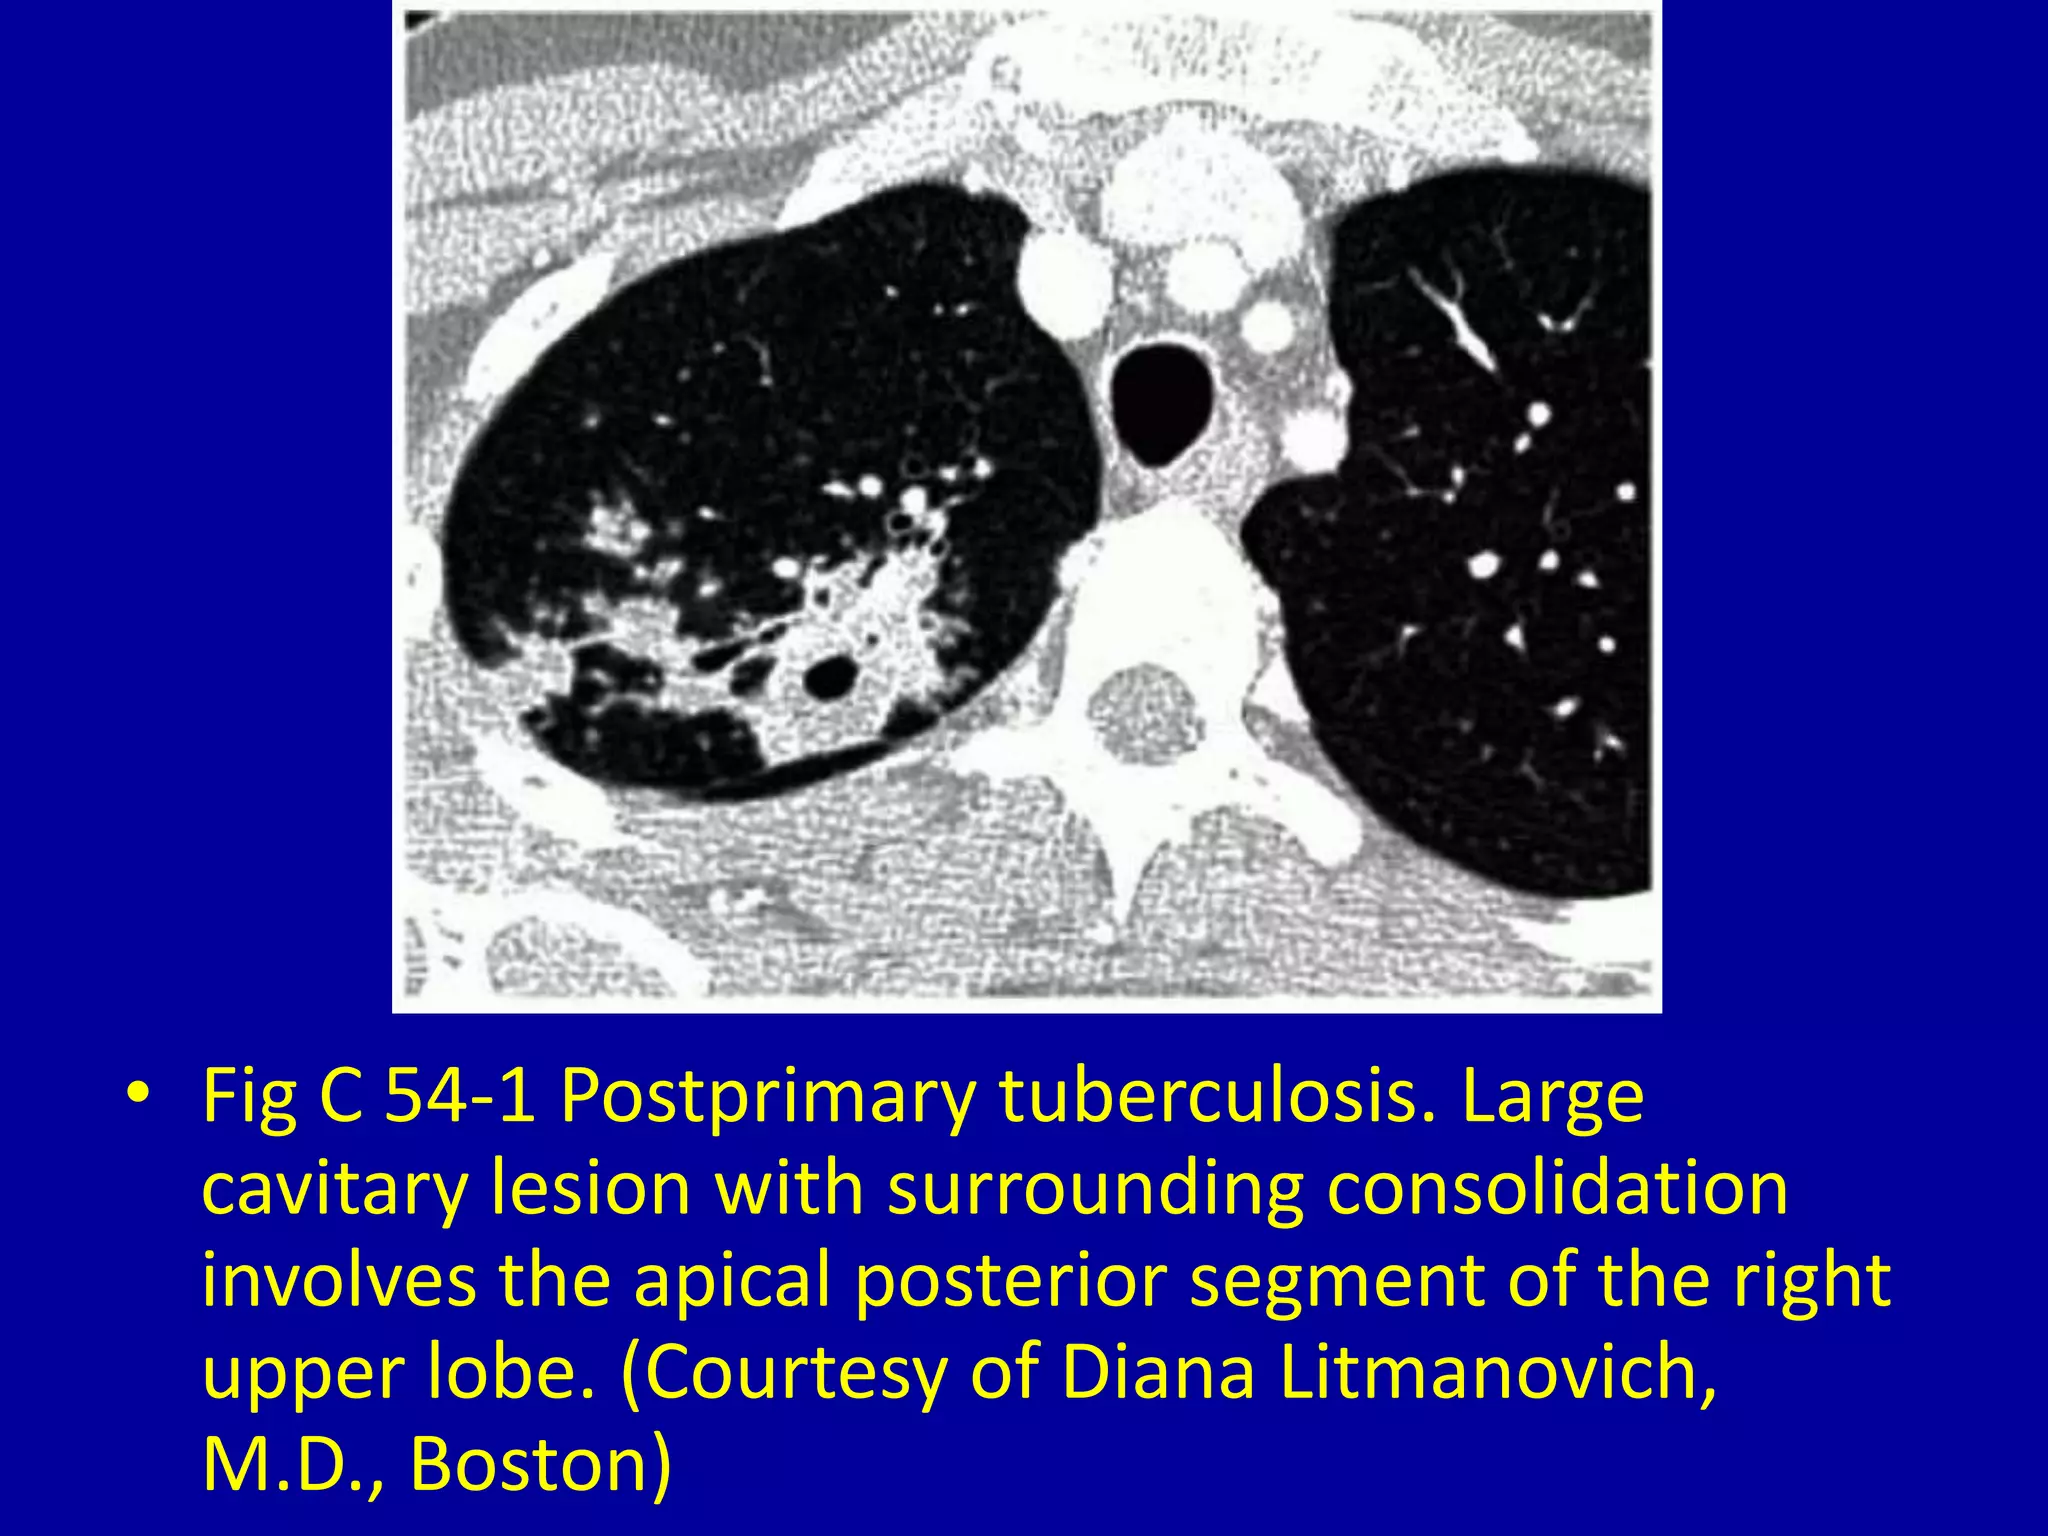

This document discusses various pulmonary diseases that predominantly affect the upper zones of the lungs. It includes 10 figures showing CT scan findings of different conditions like postprimary tuberculosis, sarcoidosis, pulmonary Langerhans cell histiocytosis, silicosis, centrilobular emphysema, chronic eosinophilic pneumonia, cystic fibrosis, allergic bronchopulmonary aspergillosis, neurogenic pulmonary edema, and ankylosing spondylitis. The images demonstrate lesions, nodules, consolidations, cysts, and other abnormalities that are largely limited to the upper lobes and regions of the lungs.